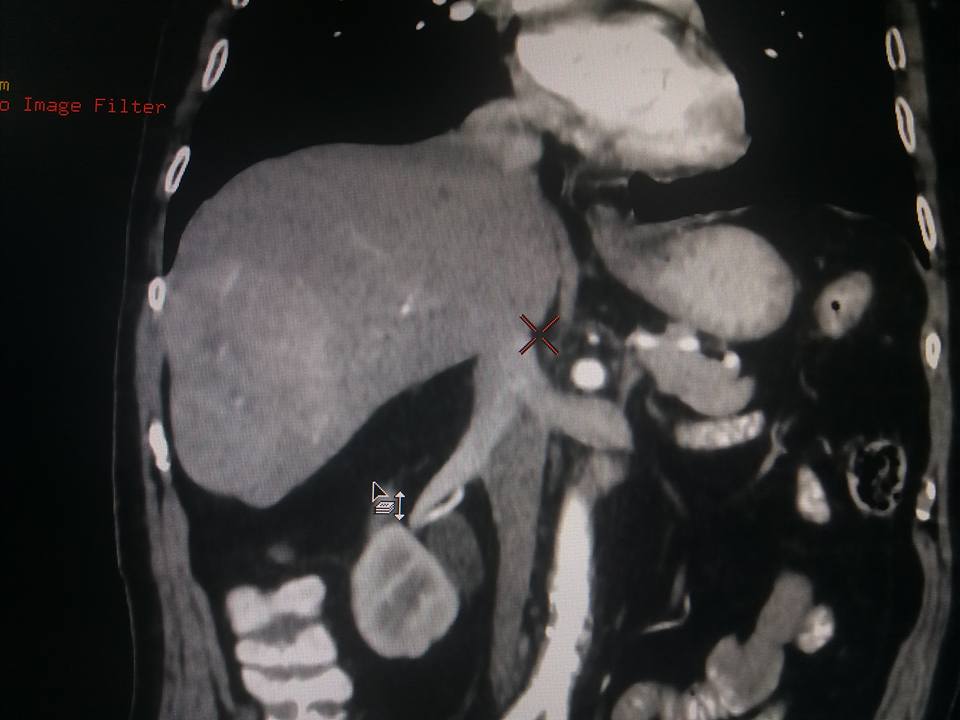

Child’s A CLD with HUGE gastric varices uncontrolled by Endoscopic glue and attempted EUS coiling. One salvage option would be TIPSS with balloon vascular occlusion but due to logistics we went for modified sugiura procedure. Splenectomy + Gastro esophageal devascularisation with anterior Gastrotomy and overseeing of gastric varices with pyloroplasty. Images show 1 CECT showing large gastric fundal varices. 2,3,4 Gastro Esophageal devasc 5, 6 Large fundal varices before and after oversewing. 7. Anterior gastrotomy 8. Pyloroplasty. Postoperative recovery was uneventful.